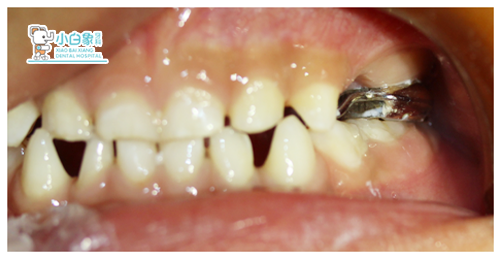

主诉:左上乳牙缺失数月。

现病史:数月前患者拔除乳牙,今特来诊。

检查:左上IV伤口愈合良好,牙龈无红肿

诊断:左上IV缺失

治疗计划:佩戴间隙保持器